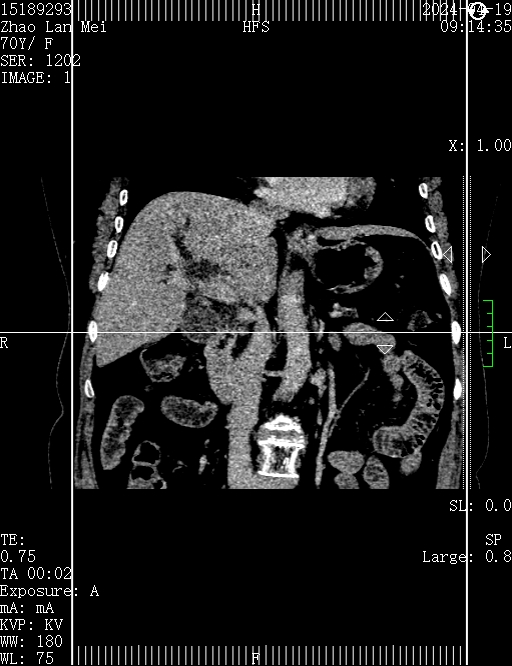

术前增强CT提示:胆总管下段占位?胆总管上段及肝内外胆管扩张